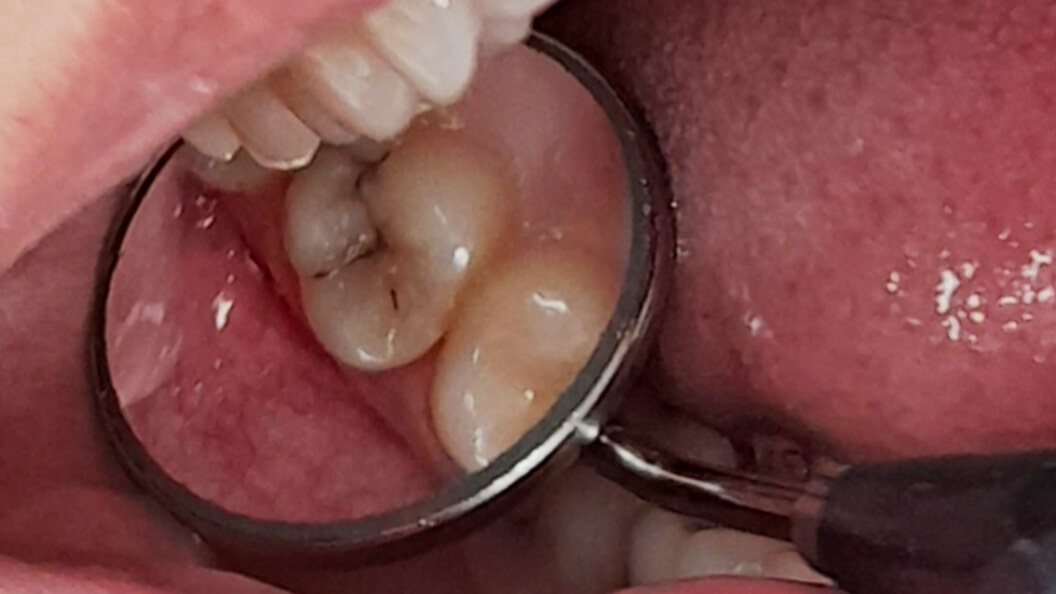

Пациентка обратилась в «Стоматологию Комфорта» с жалобами на кратковременную боль от холодного в области 17 зуба. Врач-стоматолог-терапевт Похилько Надежда Геннадьевна в ходе осмотра выявила кариозную полость на окклюзионной поверхности 17 зуба. Зондирование было болезненно, перкуссия — безболезненна. После препарирования под контролем кариес-маркера был поставлен диагноз: глубокий кариес окклюзионной поверхности 17 зуба. Врач пришёл к выводу о лечении с последующей установкой пломбы из светоотверждаемого композита Estelite.

- препарирование кариозной полости под контролем кариес-маркера;